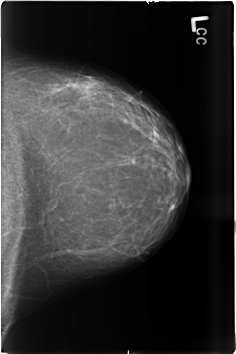

B_3482_1.LEFT_CC

LEFT_CC LINES 4592 PIXELS_PER_LINE 3056 BITS_PER_PIXEL 12 RESOLUTION 50 NON_OVERLAY